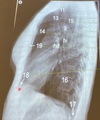

Que estructura anatómica esta en el numero 11

Traquea

41

Que estructura anatómica esta en el numero 13

Vasos supra aórticos

42

Que estructura anatómica esta en el numero 15

Espacio retro traqueal

43

Que estructura anatómica esta en el numero 9

Cayado aórtico

44

Que estructura anatómica esta en el numero 14

Espacio aéreo retro-esternal

45

Que estructura anatómica esta en el numero 19

Esternón

46

Que estructura anatómica esta en el numero 18

S.Cardiofrenico